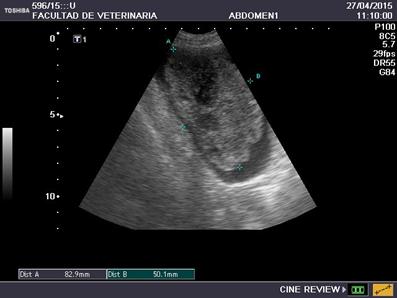

En el estudio ecográfico abdominal se observó una neoformación heterogénea a nivel de la región ventral del cuerpo de la vejiga, de 8,2 x 6,5 cm aproximadamente, con bordes irregulares, irrigada, ocupando parte de la luz de dicho órgano y que no involucraba el trígono vesical(Figura 4). Los riñones presentaban tamaño y ecoestructura conservada, acorde a la edad del paciente. En el resto del abdomen no se observaron alteraciones.

Figura 4: Primer ecografía vesical con presencia de neoformación heterogénea, con bordes irregulares, de 8,2 x 6,5 cm ocupando casi la totalidad de la luz del órgano, no afectando el trígono vesical.